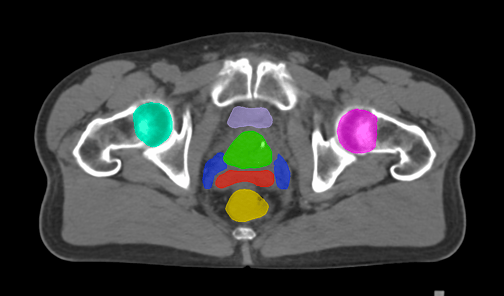

The Pelvis lymph node region encompasses lymph nodes that include the obturator lymph nodes, internal and external iliac lymph nodes (limited anteriorly at the level of the femoral heads), and extends up to the common iliac lymph nodes, covering the L5/S1 region.

Pelvis